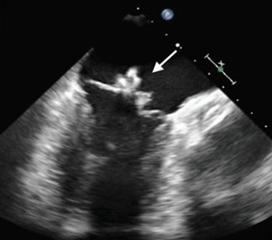

しばしば抜歯、あるいはカテーテル処置などにより、循環血液中に細菌が侵入すること(菌血症)が契機となる。このとき、上記のような素地となる疾患によって血流ジェットが生じ、心内膜が傷ついていた場合、ここに付着した細菌が感染巣(疣贅)を形成し、感染性心内膜炎を引き起こすこととなる。起炎菌としては、口腔内常在菌である緑色連鎖球菌や黄色ブドウ球菌が多く、弁尖などを破壊することによる心不全がもっとも危険である。

治療としては、原因菌に感受性のある抗菌剤を4週間ほど静脈注射する。弁疣贅が大きい場合は手術で切除することもある。